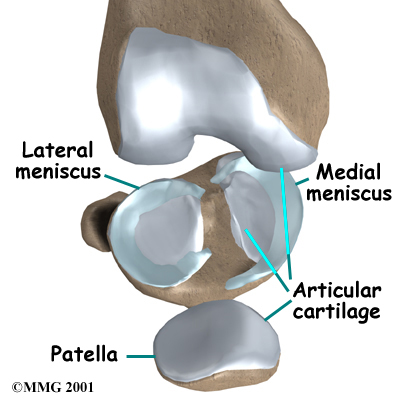

There is one meniscus on each side of the knee joint. The C-shaped medial meniscus is on the inside part of the knee, closest to your other knee (medial means closer to the middle of the body.) The U-shaped lateral meniscus is on the outer half of the knee joint (lateral means further out from the center of the body.)

There is one meniscus on each side of the knee joint. The C-shaped medial meniscus is on the inside part of the knee, closest to your other knee (medial means closer to the middle of the body.) The U-shaped lateral meniscus is on the outer half of the knee joint (lateral means further out from the center of the body.)

The menisci (plural for meniscus) protect the articular cartilage on the surfaces of the thighbone (femur) and the shinbone (tibia) and help to create a deeper joint surface, which aids in joint stability. Articular cartilage is the smooth, slippery material that covers the ends of the bones that make up the knee joint, as well as most other joints. The articular cartilage allows the joint surfaces to slide against one another without damage to either surface.

The menisci (plural for meniscus) protect the articular cartilage on the surfaces of the thighbone (femur) and the shinbone (tibia) and help to create a deeper joint surface, which aids in joint stability. Articular cartilage is the smooth, slippery material that covers the ends of the bones that make up the knee joint, as well as most other joints. The articular cartilage allows the joint surfaces to slide against one another without damage to either surface.